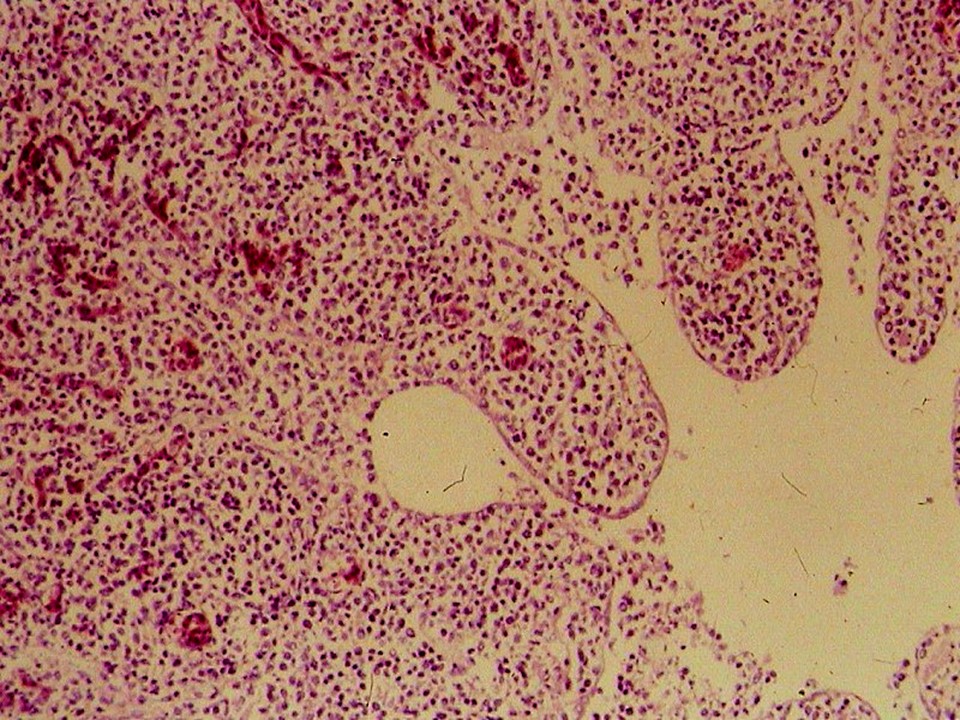

疾病中文名稱:馬立克病

疾病英文名稱:Marek's disease

影像說明:翼神經受侵犯而翅膀下垂,坐骨神經受侵犯呈劈腿狀